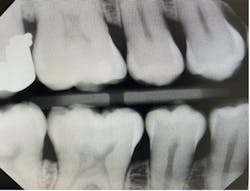

“Horizontal angulation refers to the positioning of the PID and the direction of the central ray in a horizontal, or side to side, plane.”6 Paralleling, bisecting, and bitewings all use similar principles of horizontal angulation and will not change according to technique. The PID needs be directed toward the center of the ring using a horizontal/parallel technique. With this correct angulation, proximal spaces will be cleared, and the radiopaque enamel with either be just touching or have a distant radiolucent line of separation. This will produce a diagnostic image (figure 4) where calculus or caries lesions will not go undetected.